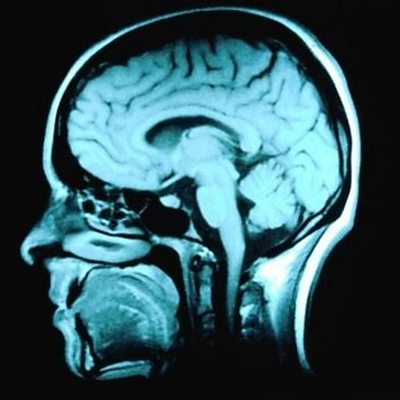

Susan Short and Ed Jones discuss potential new treatments for brain tumours.